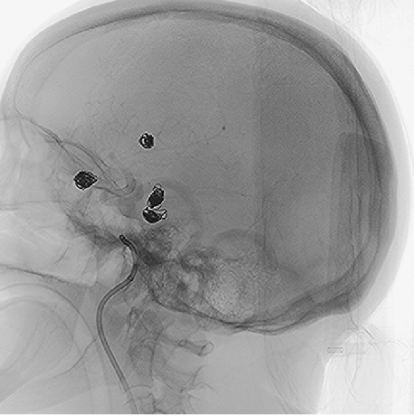

After successfully treating the left-sided aneurysms, the team proceeded to use the Nuva® Flow Diverter for the right posterior communicating artery aneurysm. The decision was made based on several advantages of the Nuva® system, including its radiopaque release-recapture segment that provides navigational guidance, full stent visibility for real-time wall apposition assessment, and the super-elastic nitinol braided structure that enhances flexibility and conformability.

According to the lesion measurements, the team selected the Nuva® Flow Diverter TJED-D-5.0-20 (designed for vessels approximately 4.5 mm in diameter and 28 mm in length).

Delivery of the Nuva® Flow Diverter

Using the TJWY Frepass®18Plus microcatheter, the Nuva® was smoothly delivered into the right middle cerebral artery. The microcatheter was then slowly withdrawn until the distal end of the stent opened into a “V”-shaped funnel configuration. At this point, the delivery system was slightly retracted to the intended anchoring position, and the stent was deployed using a controlled push-and-pull technique.

Immediate post-procedure angiography

Post-deployment angiography confirmed clear stent visibility, excellent wall apposition, unobstructed distal vessels and branches, and obvious contrast stagnation within the aneurysm sac—showing a distinct “crescent sign.” The delivery system was then successfully retrieved.

Clear visualization of the stent